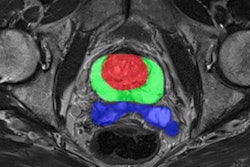

In its announcement, Quibim highlighted its QP-Prostate, QP-Brain, QP-Liver, and QP-Insights, which are cleared for use in the European Union and U.K. through the CE and UKCA marks, some of which are 510(k) cleared by the U.S. Food and Drug Administration (FDA).